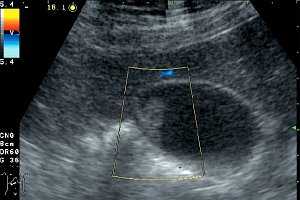

(Левый) Положение пациента на боку. На продольном УЗ срезе визуализируется смещающийся книзу под действием гравитации эхогенный сладж, формирующий сгусток.

(Правый) На продольном УЗ срезе у этого же пациента в положении на боку определяется смещающийся книзу под действием гравитации эхогенный сладж, также виден «мерцающий» артефакт.